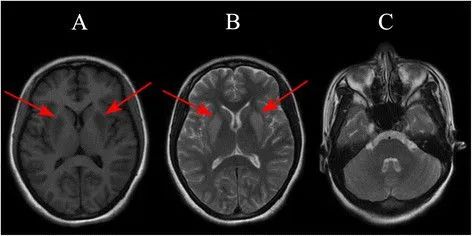

(3)EPM,病灶多对称位于基底核团或丘脑,少数病例可累及皮层,信号表现与 CPM 相似,但病灶形态不相同

对称性壳核受累,桥脑未见病灶

对称性壳核和尾状核受累,扩散受限